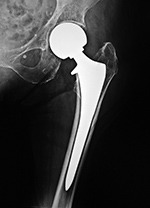

Total Hip Replacement

Total hip arthroplasty (THA) is the most common total hip replacement. It uses two components, a stemmed femoral component with a prosthetic femoral head and a prosthetic acetabular component (figure: modular total hip arthroplasty; figure: bilateral total hip arthroplasty). In 2011 there were 306,000 total hip replacements which is only second to 645,062 total knee replacements (AAOS). There were also estimated to be 105,509 partial hip replacements.

are modular. The acetabular shell, acetabular liner, femoral head, and femoral stem are separate pieces (figure: modular total hip arthroplasty). This allows the surgeon to customize each prosthesis for size and fit. Unfortunately, this can sometimes create problems at the interfaces between the modular components with disengagement and fretting. Classically, the articulating surface between the femoral head and the acetabular lining is metal (femoral head) against polyethylene (acetabular lining).

If cementless fixation is used, the component is "press fit" into place, usually into a cavity somewhat smaller than the component itself. It is common to see fixation screws with the acetabular component which are often included for patients with significant acetabular bone loss or because of

surgeon preference (figure: bilateral total hip arthroplasty). Rough or porous surfaces on the prosthetic materials facilitate bone ingrowth and are usually the basis for cementless fixation. The surfaces may be treated with bioactive

For patients younger than 65 with a normal life expectancy and adequate bone mass, cementless femoral stems are preferred (figure: bilateral total hip arthroplasty in 38 year-old man). It is possible that a femoral stem which has become well ingrown will not require revision, even if the acetabular component, and the articulating femoral head may need revision in the future. However, as in most cases with orthopedic surgery, the choice of components and the use of cemented or cementless femoral component depends on the surgeon's preference and experience. With any type of joint replacement, there is concern for its longevity and the need for ultimate revision or complete replacement. Revision surgery is usually not easy and may not have good results. Therefore, joint replacement is avoided as much as possible in younger patients and put off as long as is reasonable.

Modular non-cemented total hip prosthesis (THA) |

Implants consist of a proximally porous coated stem and prosthetic head and a porous coated metal acetabular component with a polyethylene liner. From Benjamin, 1994 |